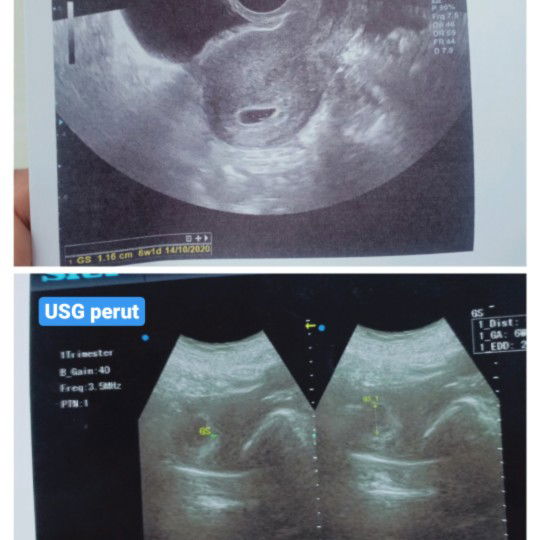

hasil usg berbeda

Halo bun aku mau tanya. Waktu aku lagi keluar kota ternyata aku lagi hamil, dan langsung usg transvaginal (pict atas) hasil usg nya aku hamil 6minggu1hari, kantong nya jelas banget tp janin belum terlihat. Setelah aku pulang dari luar kota 2minggu kemudian aku usg lagi, usg perut (pict bawah) harusnya sudah hamil 8minggu, tapi hasil usg nya malah 6minggu 5hari, kantong samar dan gak jelas, janin juga belum terlihat. Apa karna kualitas alat usg nya kurang bagus ya? Ada yg pernah ngalamin juga gak hasil usg nya bisa beda gitu? Dan bunda yg udah hamil, usia berapa janin nya udah terlihat?